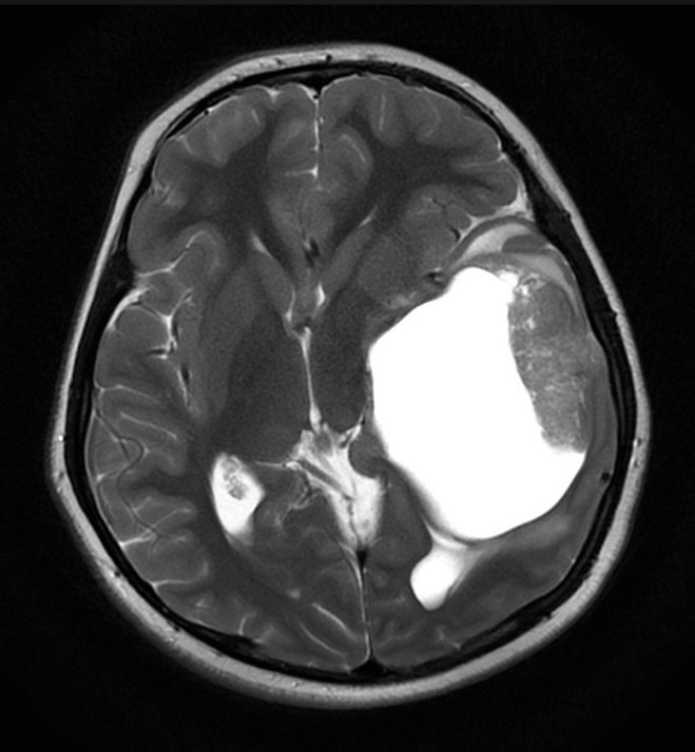

Santral Sinir Sisteminin Basit Anatomisi Sinir sistemi genel olarak santral sinir sistemi ve periferik sinir sistemi olarak ikiye ayrılır. Santral sinir sistemi beyin, beyin sapı, beyincik ve omurilikten oluşur. Periferik sinir sistemi ise omurilikten çıkan spinal sinirler ve otonom sinir sisteminden oluşur. MENİNKSLER (BEYİN ZARLARI) Beyin ve omurilik, kendisini darbelerden koruyan kranium ve omurga kanalı […]